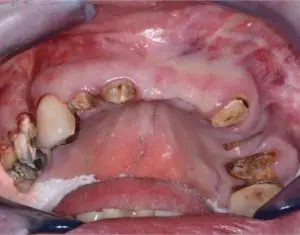

Missing Teeth Indicate Greater Risk of Cardiovascular Disease 2019-10-05 Adults who have lost teeth due to nontraumatic reasons may have a higher risk of developing cardiovascular disease, according to the American College of Cardiology